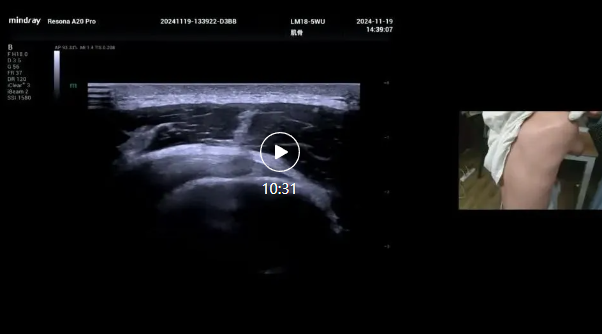

肩关节超声演示,蓝蓓老师,广西区人民医院超声科,2024年